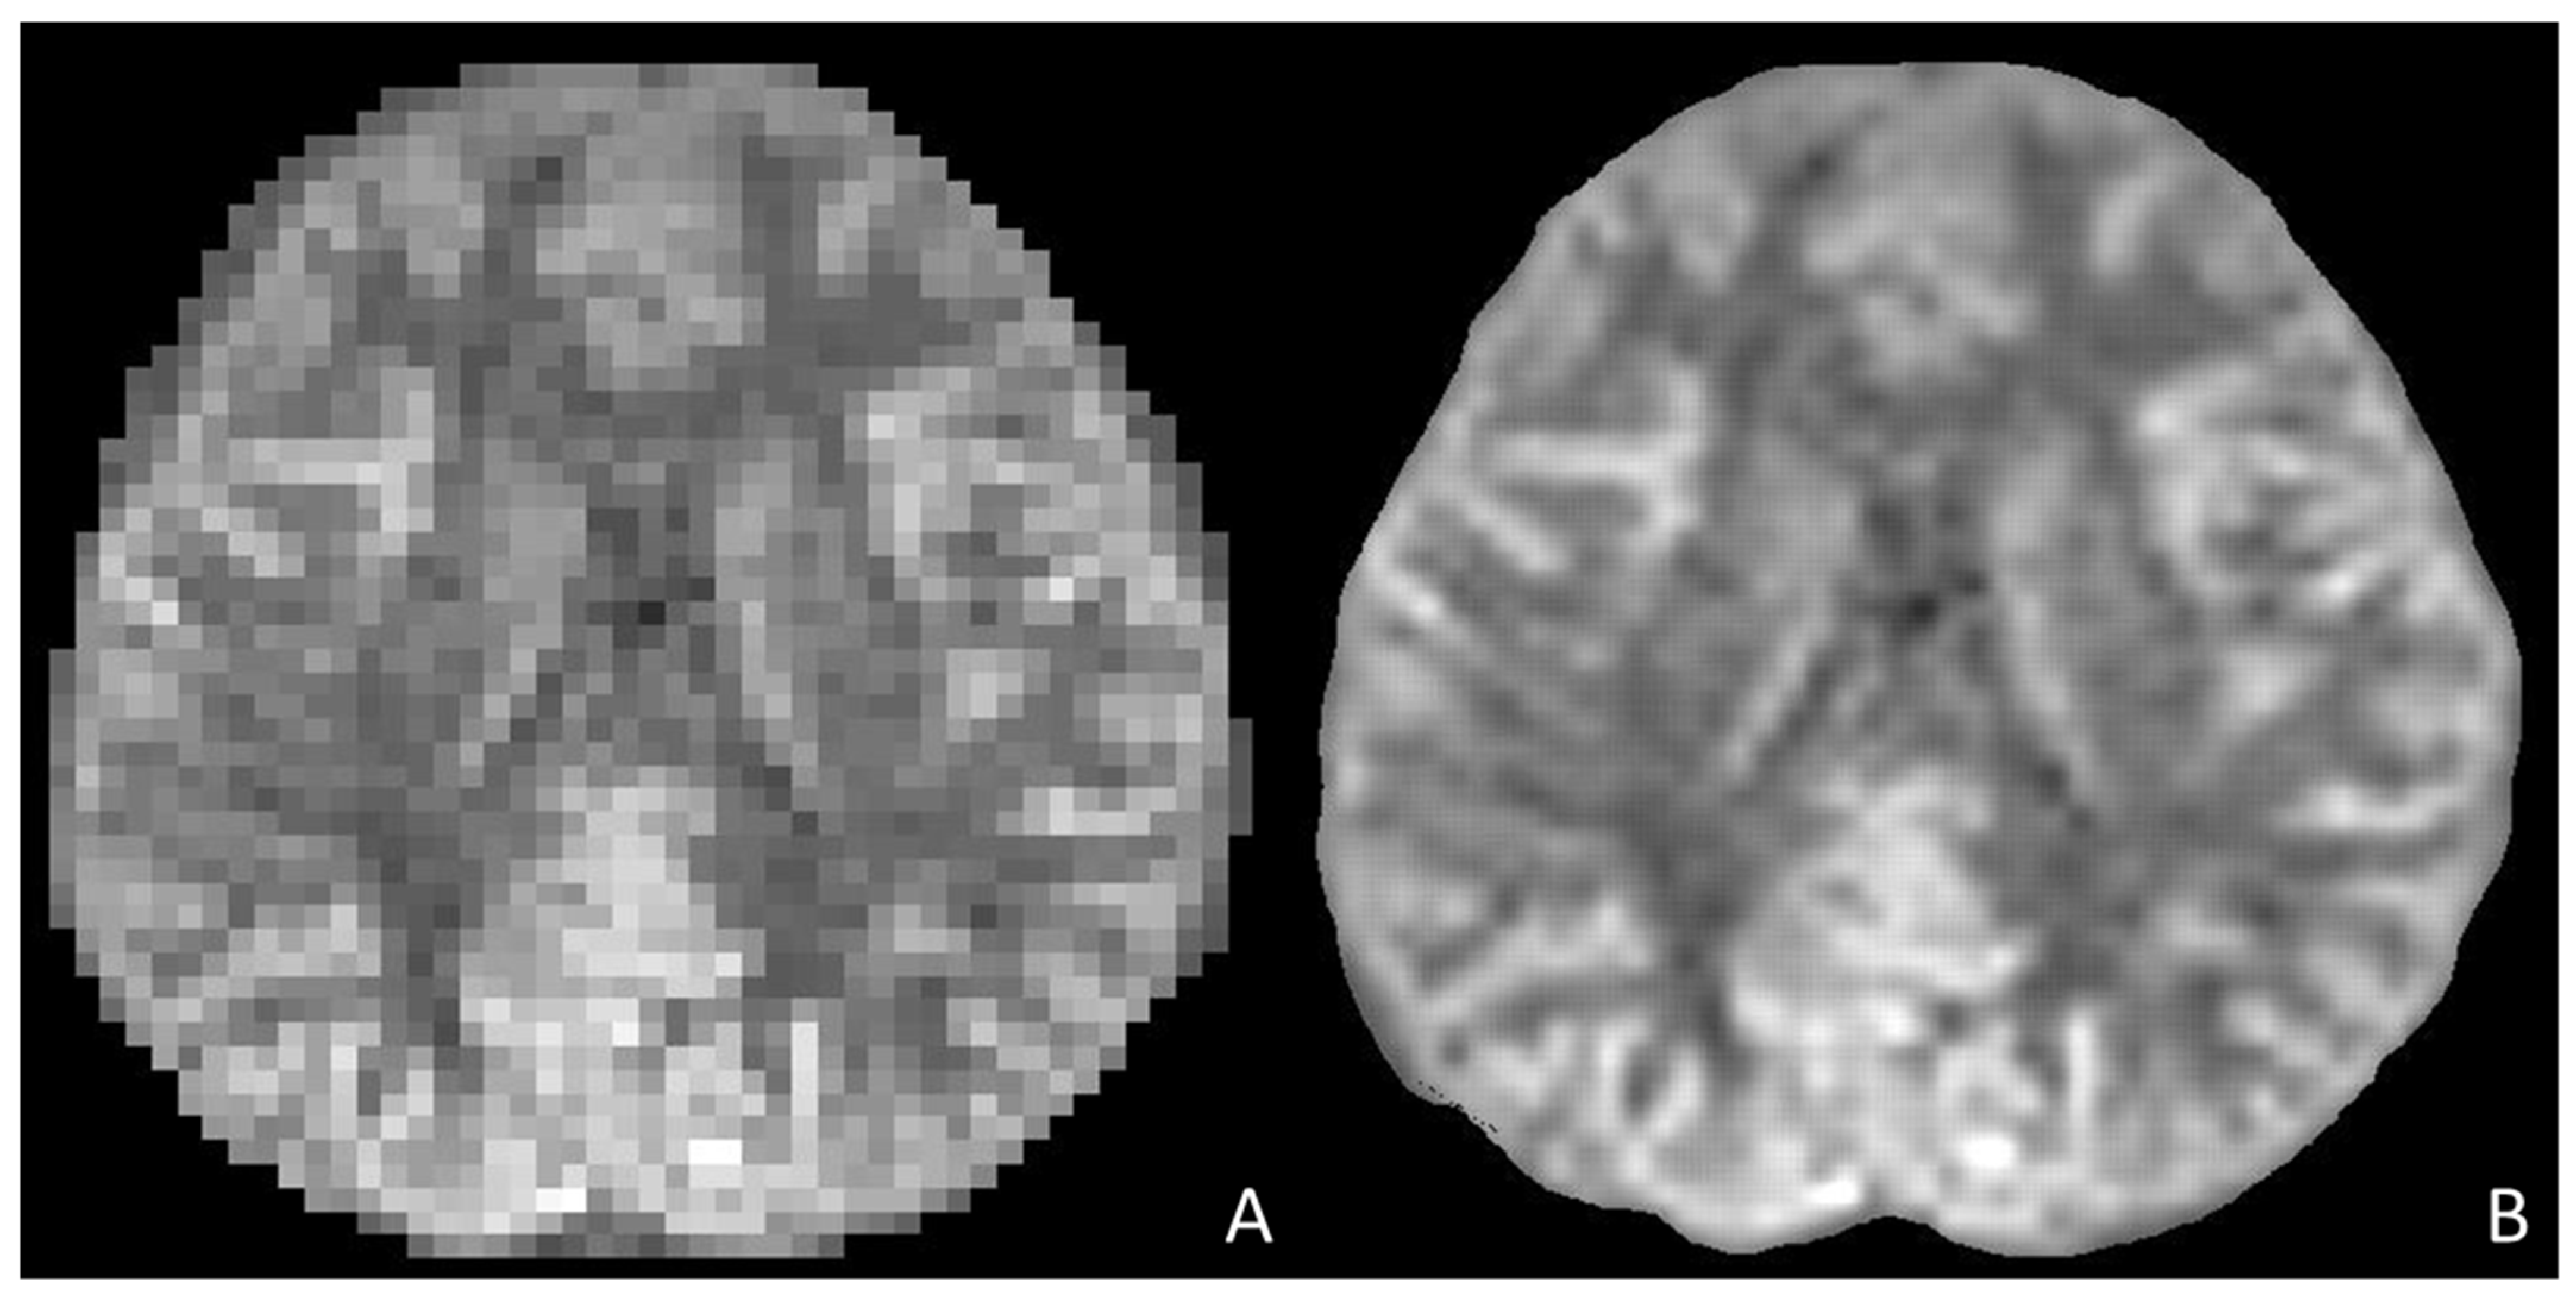

- Molina-Maza, J.M.; Galiana-Bordera, A.; Jimenez, M.; Malpica, N.; Torrado-Carvajal, A. Development of a Super-Resolution Scheme for Pediatric Magnetic Resonance Brain Imaging Through Convolutional Neural Networks. Front. Neurosci. 2022, 16, 830143. [Google Scholar] [CrossRef] [PubMed]

- Zhang, S.; Zhong, M.; Shenliu, H.; Wang, N.; Hu, S.; Lu, X.; Lin, L.; Zhang, H.; Zhao, Y.; Yang, C.; et al. Deep Learning-Based Super-Resolution Reconstruction on Undersampled Brain Diffusion-Weighted MRI for Infarction Stroke: A Comparison to Conventional Iterative Reconstruction. AJNR Am. J. Neuroradiol. 2025, 46, 41–48. [Google Scholar] [CrossRef]

- Matsuo, K.; Nakaura, T.; Morita, K.; Uetani, H.; Nagayama, Y.; Kidoh, M.; Hokamura, M.; Yamashita, Y.; Shinoda, K.; Ueda, M.; et al. Feasibility Study of Super-Resolution Deep Learning-Based Reconstruction Using K-Space Data in Brain Diffusion-Weighted Images. Neuroradiology 2023, 65, 1619–1629. [Google Scholar] [CrossRef]